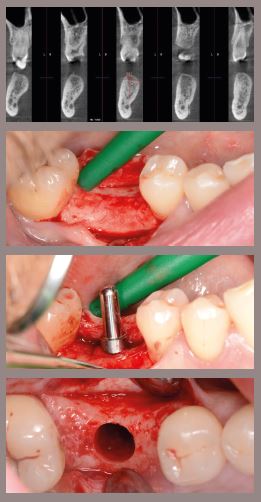

CONTEMPORARY BONE GRAFTING

LECTURE TOPICS

• Implant site anatomy and evaluation

• Grafting materials (Autologous, Xeno-, Allograft…)

• Membrane selection and fixation techniques

• Bone harvesting techniques

• Flap design and suturing

• Bioactive modifiers, sticky-bone

• Socket grafting

• Vertical and horizontal GBR

• Veneer Grafting

• Post op protocol, medication

HANDS-ON:

1. Socket grafting, Ice-cone techniques

2. Vertical augmentation and membrane fixation

3. Flap designs and tension-free suturing